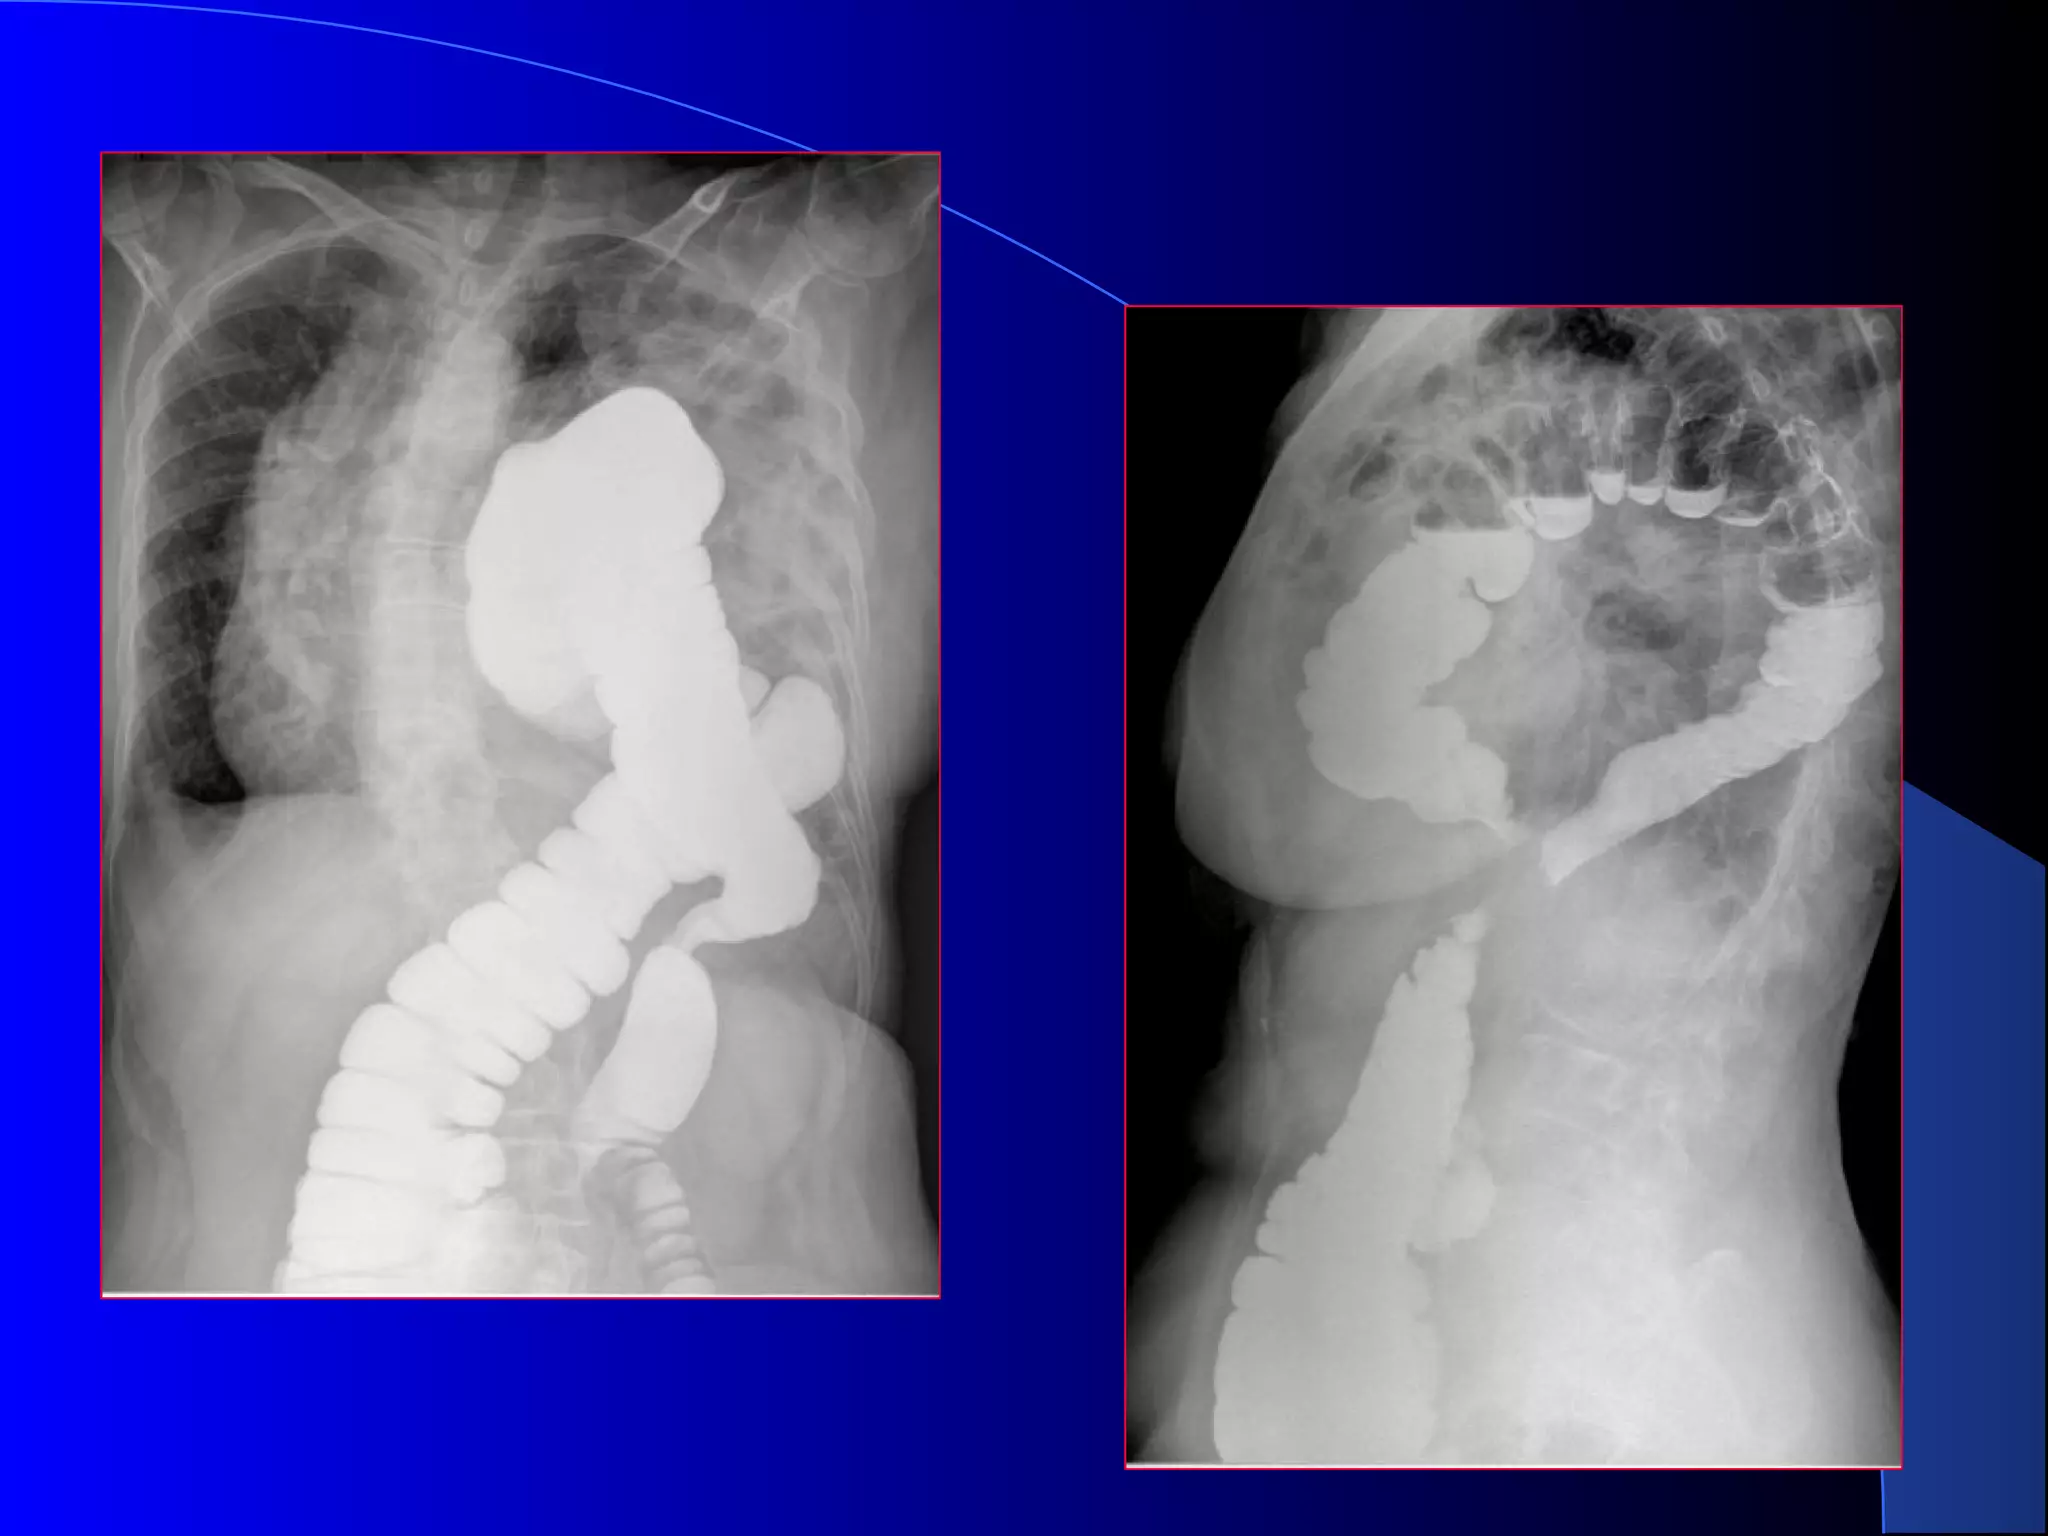

Hernie difragmaticaHernie difragmatica

posttraumaticaposttraumatica

Traumatism cu volet costal ,ruptura de diafragm si hernie

diafragmatica postraumatica

 imagine aerica localizata

in hemitoracele stang care

simuleaza un pneumotorax

•tranzitul cu substanta de

contrast precizeaza

diagnosticul de hernie

diafragmatica si organl

herniat

Hernie difragmaticaHernie difragmatica posttraumaticaposttraumatica Traumatismcu volet costal ,ruptura de diafragm si hernie diafragmatica postraumatica  imagine aerica localizata in hemitoracele stang care simuleaza un pneumotorax

•tranzitul cu substantade contrast precizeaza diagnosticul de hernie diafragmatica si organl herniat